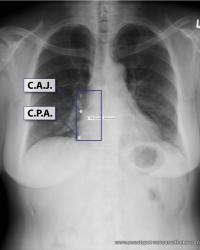

Figure - 01

CXR Sweet Spot™ Box Measurements |